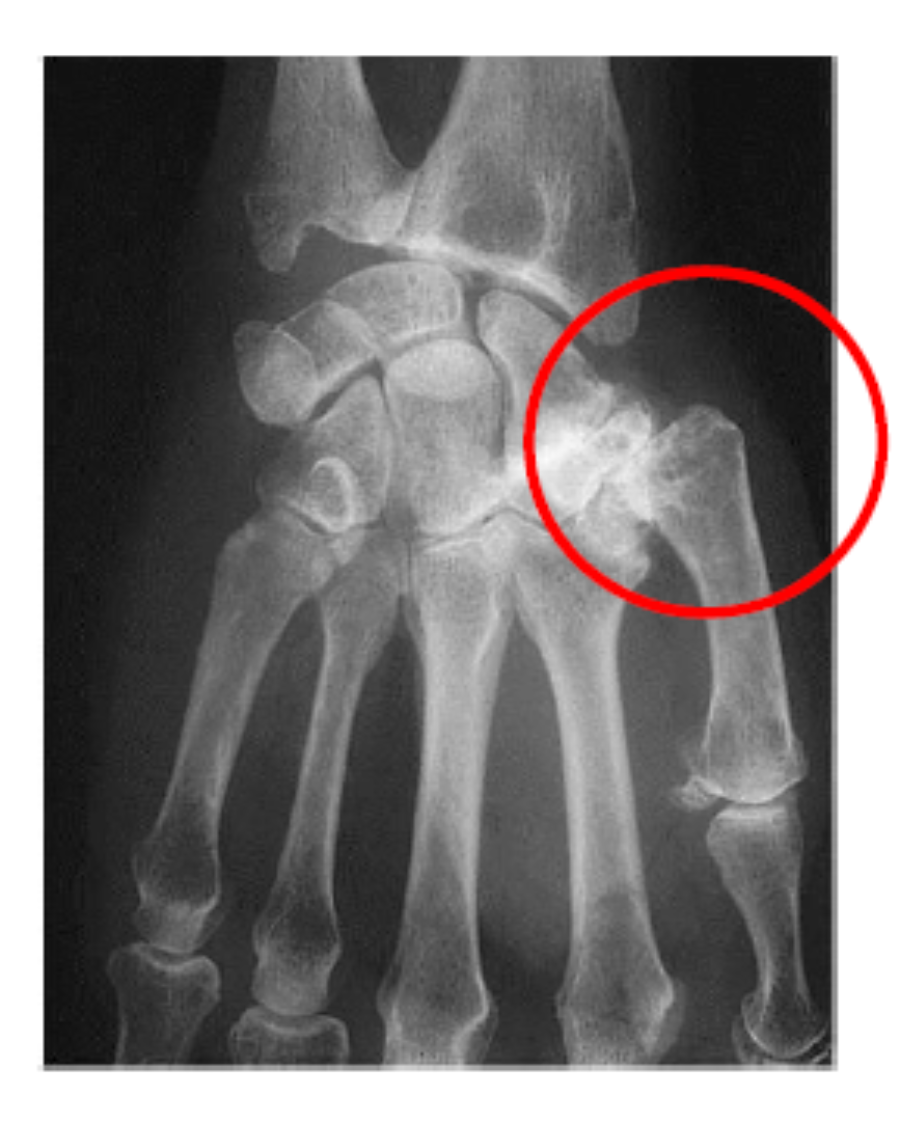

Imagem: diminuição do espaço articular, esclerose subcondral, neoformação óssea, osteófitos

O que são os nódulos de Bouchard e Heberdan?

O que é rizartrose?

Acometimento articular de interfalangianas devido a neoformação óssea da osteoartrose

Nódulo de Heberdan: interfalangianas distas

Nódulo de Bouchard: interfalangianas proximais

Rizartrose: envolvimento da primeira metacarpo-falangiana (MCF)